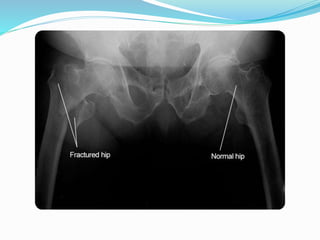

Exams and tests

X ray of bones

•Diagnose bone loss and osteoporosis

•Predict your risk of future bone fractures

•See how well osteoporosis medicine is working

A spine or hip x-ray may show fracture or collapse of the

spinal bones. However, simple x-rays of other bones are not very

accurate in predicting whether you are likely to have

osteoporosis.

Exams and tests Xray of bones •Diagnose bone loss and osteoporosis •Predict your risk of future bone fractures •See how well osteoporosis medicine is working A spine or hip x-ray may show fracture or collapse of the spinal bones. However, simple x-rays of other bones are not very accurate in predicting whether you are likely to have osteoporosis. You may need other blood and urine tests if your osteoporosis is thought to be due to a medical condition, rather than simply the usual bone loss seen